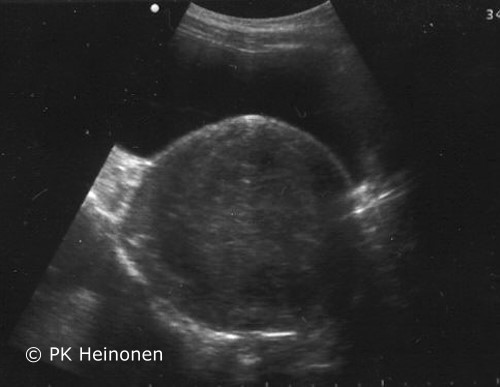

Myoma in Ultrasonography

Myoma in ultrasonography. A large (10 cm) myoma in the anterior wall of the uterus behind the urinary bladder seen in abdominal ultrasonography. The myoma caused an acute urinary retention.

Picture: Pentti K. Heinonen